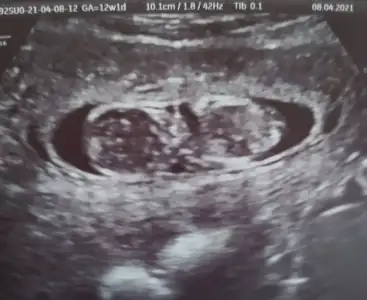

dr soylemeden siz gorun genital nub teorisi ( bebegin cinsiyeti)

Ikra meyra Ikra meyra canim 12+2 bı tahmin de bulunurmusun.İlk bebeğimi bilmistin ya.bunada yorum yaparsan sevinirim.tesekkurler .

• IMG_20210408_180440.webp

IMG_20210408_180440.webp

21,8 KB · Görüntüleme: 87

• IMG_20210408_180426.webp

IMG_20210408_180426.webp

29 KB · Görüntüleme: 79

• IMG_20210408_180406.webp

IMG_20210408_180406.webp

28,9 KB · Görüntüleme: 82

• IMG_20210408_180340.webp

IMG_20210408_180340.webp

21,5 KB · Görüntüleme: 69